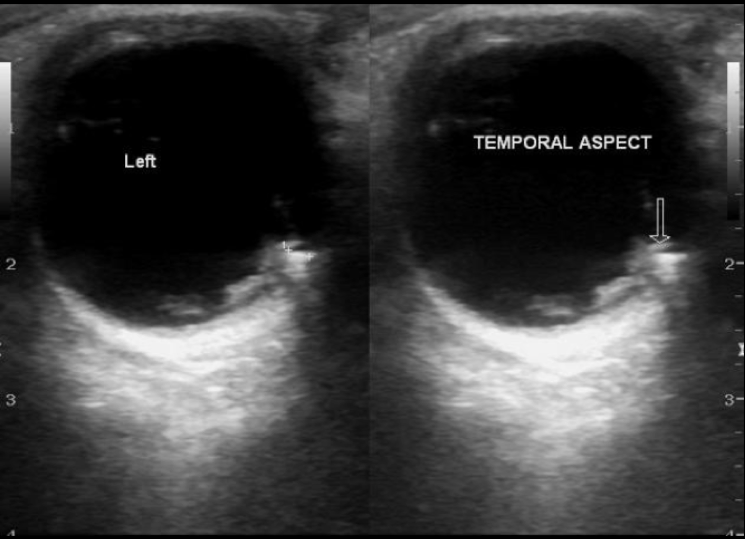

Figure 1: Linear hyperechoic area without acoustic shadowing

CASE RESOLUTION

In this case, a hyperechoic foreign body with posterior shadowing was identified on ultrasound. After anesthetic was applied, a small incision was made in the skin that allowed for easy removal. The object was a small wooden splinter. Ultrasound was then used to assess and there was no remaining material so the patient was discharged.